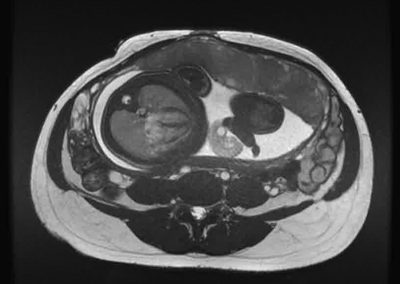

L’Université Paris Cité franchit une nouvelle étape dans le domaine de l’imagerie médicale anténatale avec l’acquisition d’un système d’Imagerie par Résonance Magnétique (IRM) 1,5T ARTIST™ de GE HealthCare. Cet équipement de pointe renforce les capacités de la Plateforme LUMIERE à l’hôpital Necker-Enfants malades, plateforme intégrée de soins, de recherche clinique et d’enseignement en imagerie médicale de la femme enceinte, du fœtus et du placenta.

Depuis 2020, la Plateforme LUMIERE offre aux femmes enceintes volontaires, entre 16 et 36 semaines d’aménorrhée et suivies à l’hôpital Necker-Enfants malades, la possibilité de participer activement à l’avancée de la recherche en médecine fœtale, tout en bénéficiant d’une IRM fœtale au cours de leur grossesse, réalisée dans un cadre sécurisé et encadré.

L’inclusion de ces patientes, depuis leur accueil jusqu’à la réalisation des examens d’imagerie, puis l’analyse des images et l’interprétation des résultats par des équipes expertes, enrichit une base de données structurée, unique au monde, au service de la recherche et de l’innovation en imagerie anténatale et en médecine fœtale.